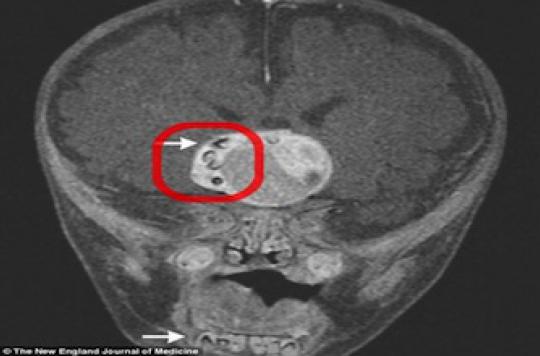

Une Tumeur Extraite Du Cerveau D Un Nouveau Ne Contenait Un Pied La Presse

Des Dents Dans Le Cerveau D Un Bebe A Cause D Une Tumeur